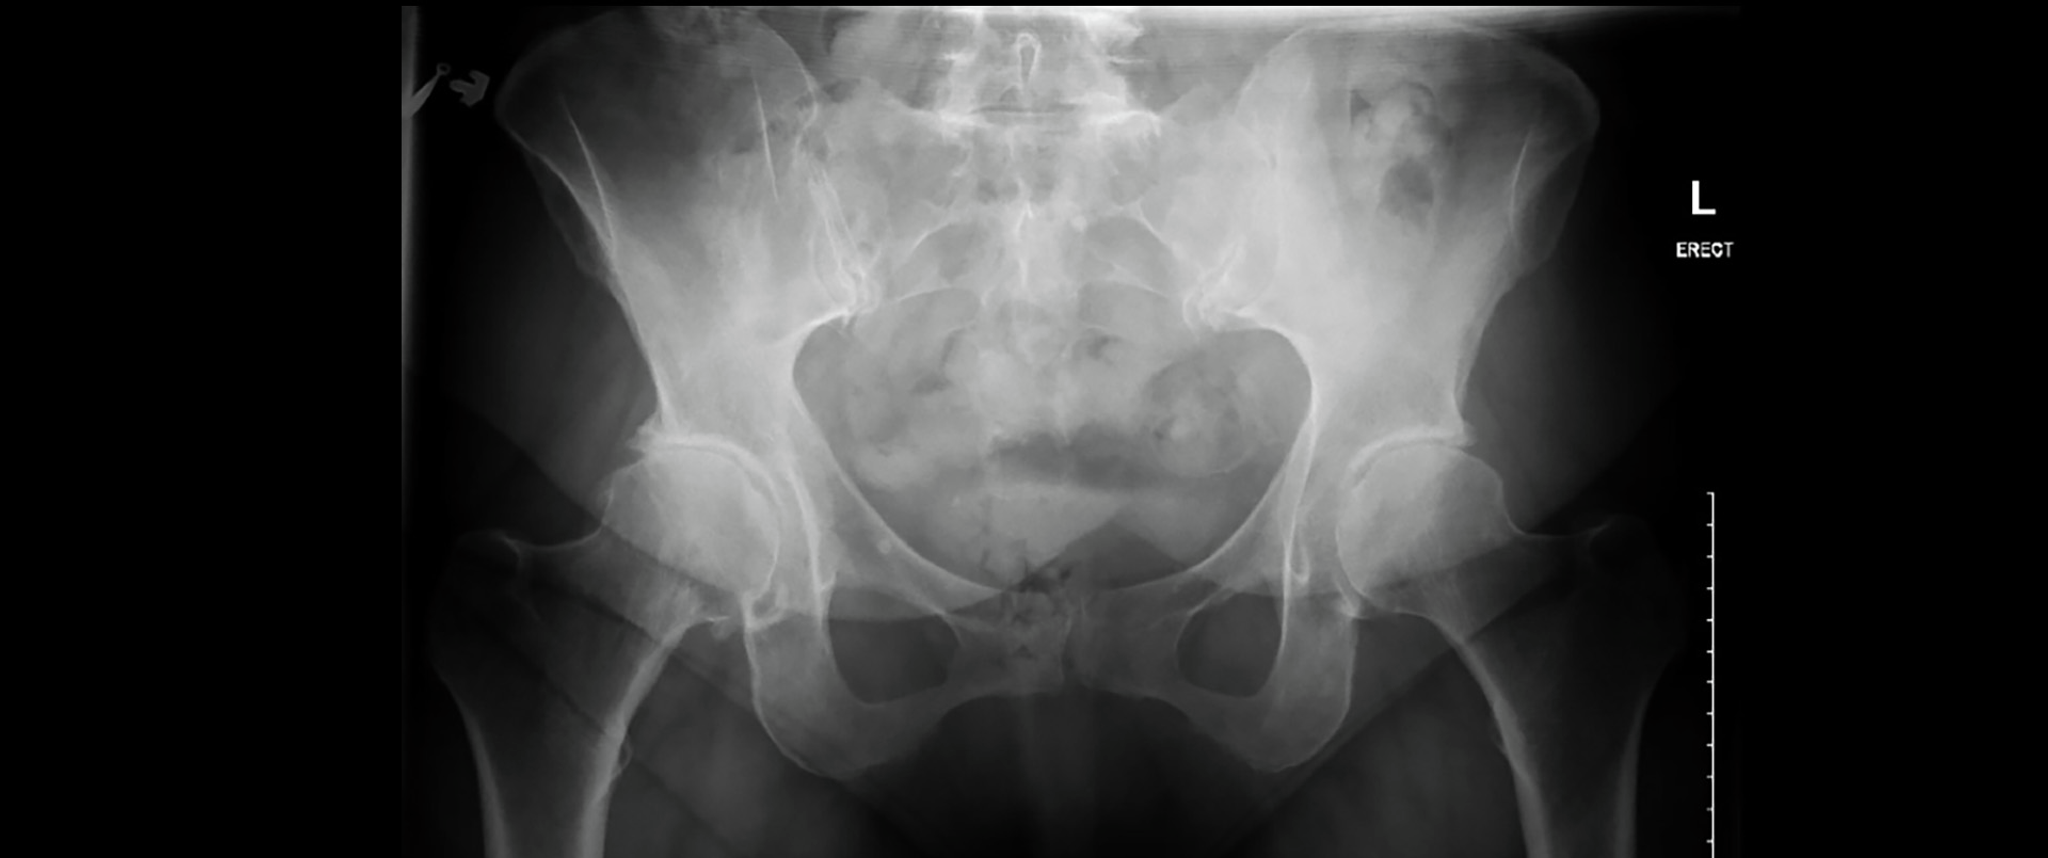

An X-ray shows the pelvis of a patient following total right hip replacement, and demonstrates the placement of a hip implant.

Three month follow up AP pelvis – well repaired, with stable components, restoration of hip biomechanics, pain free ambulation, and patient's return to active lifestyle.

Mrs. M was ambulating without an assistive device and off of narcotic pain medications at her two-week follow-up appointment. At three-months, she reported no residual right hip pain, and the resumption of normal activities. Her incision was well healed, and her strength, hip flexion, and abduction were normal (5/5).